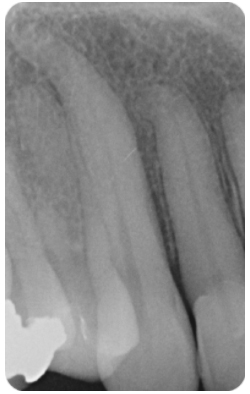

- The apical foramen is not always located at root terminus (Figures 1 and 2). There can be up to 3mm variation in 50-98% of roots. It is generally greater in posterior teeth

Figure 2a: Master cone radiograph. The apical foramen exits the root laterally on the mesial root. An apex locator is essential in these cases to determine the WL. b) Mid-fill radiograph - The distance between with apical constriction and root terminus increases with age due to secondary cementum deposition at the root apex (Figure 1)

- Two dimensional: radiographs are two-dimensional images and offer a limited perspective particularly in the bucco-lingual plane (Figure 4)

Figures 4: Radiographs are two-dimensional images offering a limited perspective in the bucco-lingual plane. This makes WL determination challenging in some cases. Root canal treatment LL6 Figure 4a) Preoperative radiograph. Figure 4b: Master cone radiograph. The four separate canals are terminating at different lengths. It would not have been possible to estimate this accurately using a preoperative radiograph, and an apex locator was essential. Figure 4c: Postoperative radiograph